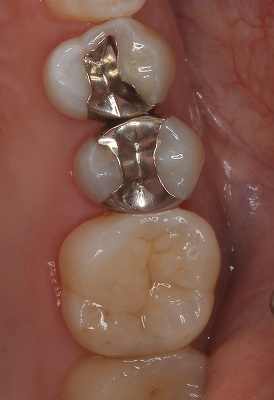

メタルアンレーが割れる!?

個人的に非常に珍しいケースなのですが、

患者さんから連絡があり、「奥の銀歯がかけた」とのこと

これだけ聞くと銀歯の周りの歯がかけたかかな!?と思っていたのですが、

実際口の中を診させてもらうと

2026EEdental KOM (1).jpg

一番したの奥歯インレーの一部が割れて無くなっている・・・

個人的に患者さんにはクリアランス(隙間)が少ないような場合、

「金属は1mm程度厚みがあれば割れない」とゴールドクラウンなどの説明しているんですが、金属が割れている。。。

金属断面を顕微鏡で観察していると、もしかして鬆が入っていたのかも!?

機能咬頭側の金属が割れていますが、そろそろ止めませんか!?この便宜形態

患者さんにはこれだけ健康な歯が残っていれば、金属でなくレジンでも大丈夫と説明しレジン充填させてもらいました。

2026EEdental KOM (2).jpg

術後(治療時間1時間)